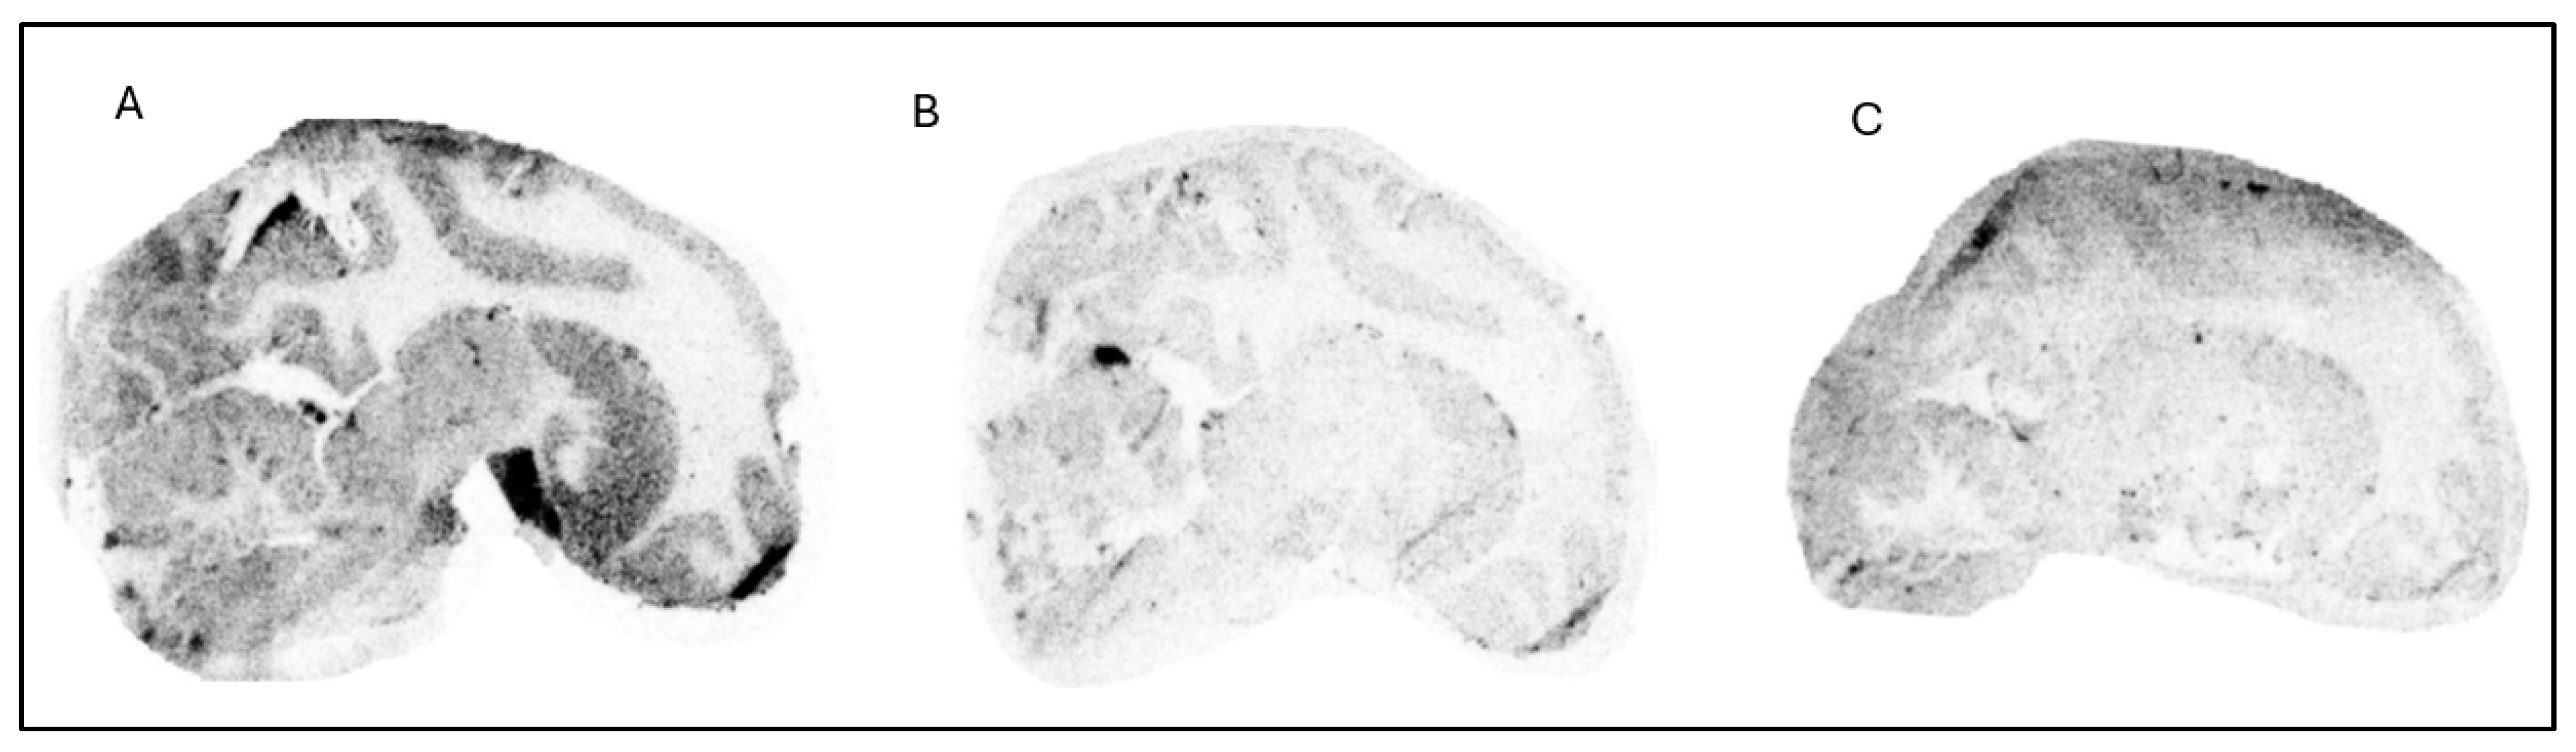

Figure 5. PET images (color scale is arbitrary) co-registered with MRI (left) and regional brain uptake of [18F]1 at baseline condition (right).

Four female cynomolgus monkeys, NHP1, NHP2, NHP3 and NHP4, were the subjects of a study involving three different radioligands, [18F]1, [18F]2 and [11C]3, as detailed in Table 2. A total of nine PET measurements were performed across nine separate experimental days. Seven of these measurements were conducted under baseline conditions, three with [18F]1, two with [18F]2, and two with [11C]3. Two additional PET measurements were conducted with [18F]1 following pretreatment with two different LRRK2 inhibitors, representing two distinct structural classes: GNE-7915 [21] and PFE-360. GNE-7915 (40 mg/kg body weight) and PFE-360 (0.5 mg/kg body weight) were administered 30 min prior to the injection of the radioligand [18F]1. [18F]1 demonstrated good brain uptake (>3%ID) with rapid washout, and regional differences in uptake suggest some specific binding to the target. The cerebellum showed the lowest uptake, indicating low binding in this region (Figure 5). However, no clear blocking effects were observed with GEN-7915 (Figure 6) or PFE-360 (Figure 7), indicating limited evidence of in vivo target-specific binding. Brain uptake of [18F]2 was high (3.8–4.4%ID at peak) with a fast washout, reaching half the peak level within approximately 20 min, and showed a relatively uniform distribution across all the brain regions (Figure 8). Conversely, [11C]3 exhibited moderate initial brain uptake (>1%ID) but rapid washout, with no significant regional differences (Figure 9). Due to the relatively uniform distribution and no regional differences, both [18F]2 and [11C]3 were considered inappropriate for further development. The free fraction in plasma (fP) was 45% for [18F]1, 60% for [18F]2 and 15% for [11C]3. For all the PET measurements with [18F]1, at baseline and following the administration of GEN-7915 and PFE-360, kinetic analysis was performed using 1TC and 2TCM with measurement of the arterial input function utilizing 90 min data (Table 3). The outcome measure was the total distribution volume VT and VT/fp. No difference in VT or VT/fp between baseline and pretreatment was observed (Table 4). There was no effect of pretreatment on fp. The main challenge for LRRK2 PET radioligand discovery is the low Bmax of LRRK2, which requires very high-affinity compounds that are not overly lipophilic.